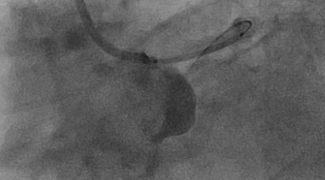

Abdul Hakeem, MD; Chunguang Chen, MD; Mark J. Russo, MD, MS

This is the first published description of edge-to-edge transcatheter mitral valve repair (ETE-TMVr) in a patient with Down’s Syndrome. This case experience suggests a potential role for ETE-TMVr in high-risk and complex congenital mitral...